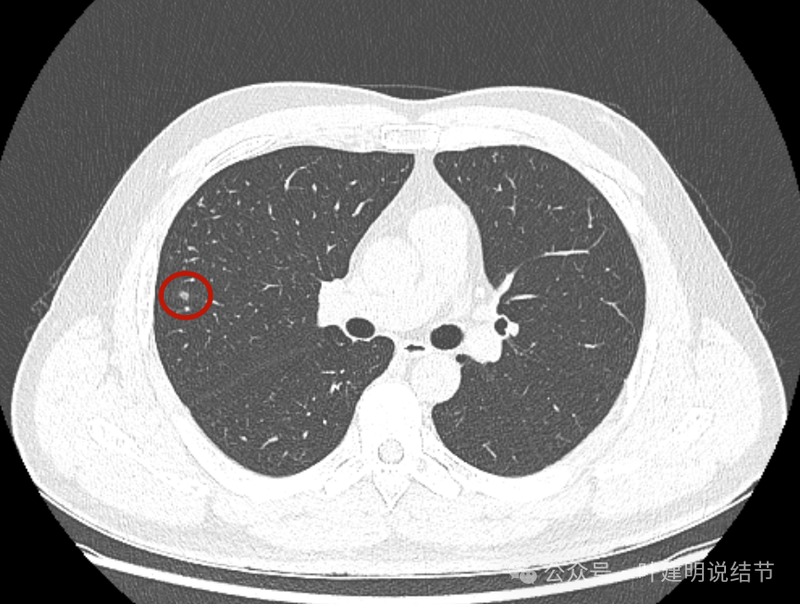

右中叶另处有斑点状多发实性结节,其中之一有小空泡征,也是轮廓与边界较为清楚的。

右中叶以及左上叶舌段也有多发偏模糊的实性结节影。

病灶出现,密度稍高。